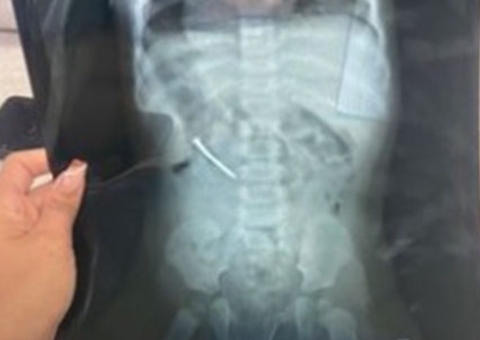

O juiz foi socorrido pela equipe médica presente no local e foi encaminhado para o hospital. Orielson ficou com escoriações, inchaço e dores no rosto.